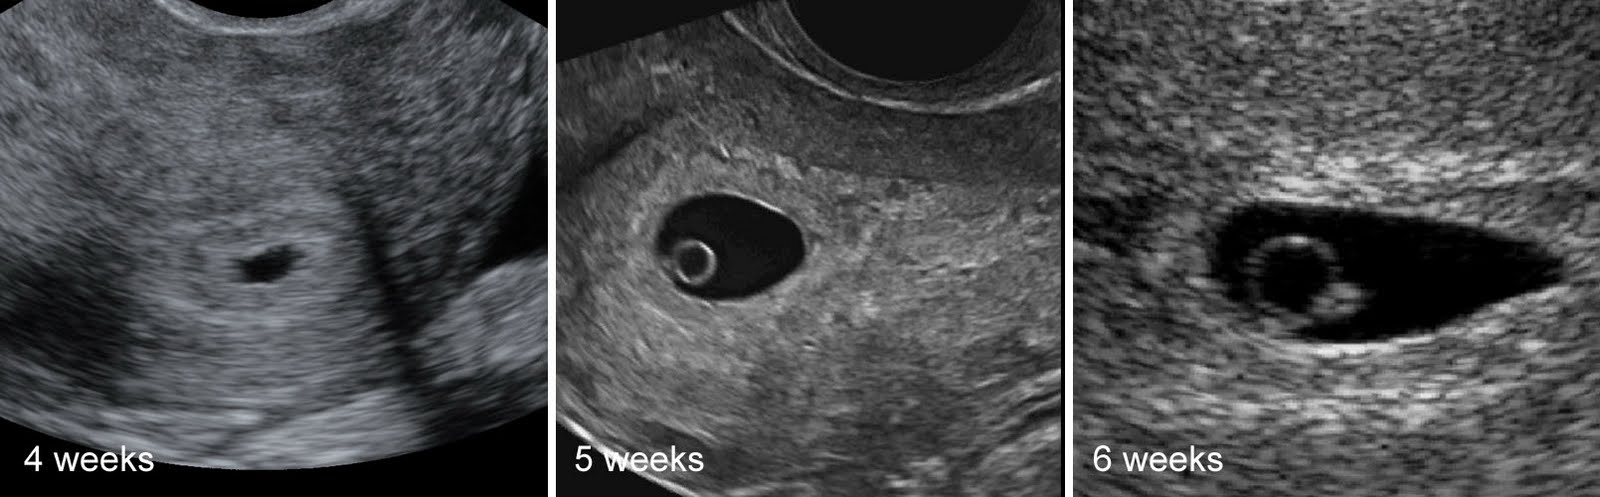

Фотографии на ранних этапах беременности

Раздел: Визуальный дайджест